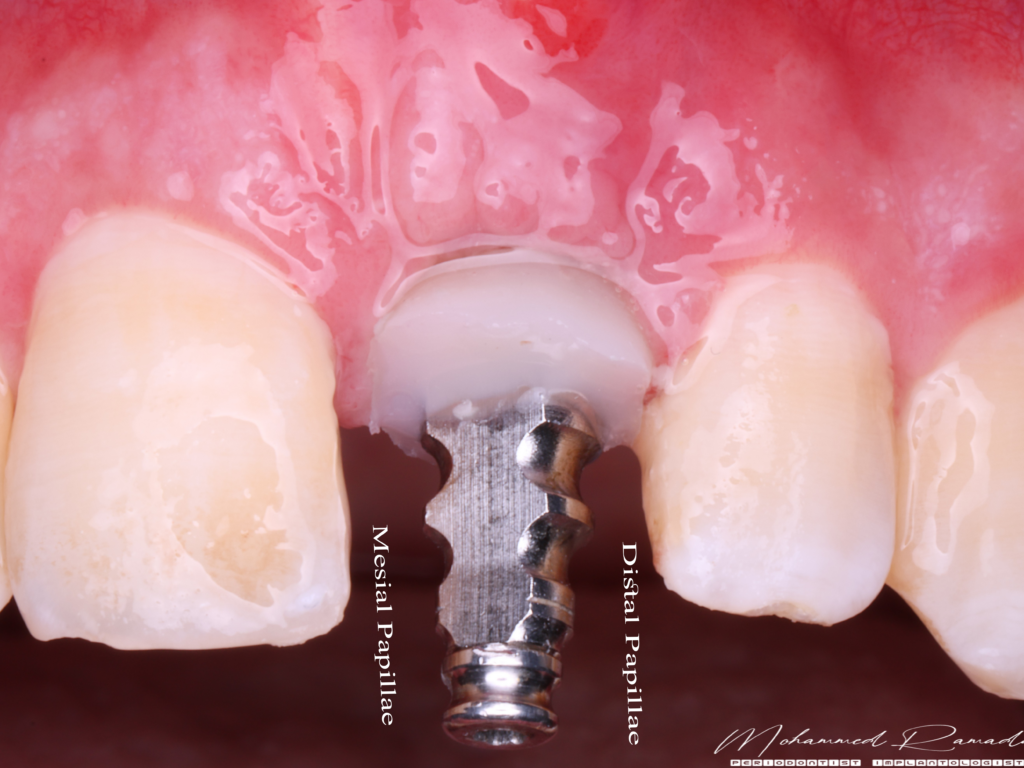

- Temporization achieved with a stock abutment, followed by a full-contour milled PMMA crown to promote papilla formation.